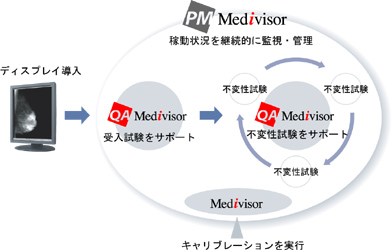

2025 国際医用画像総合展(ITEM 2025)」に出展 | 株式会社JVC, ソフトウェア | 製品情報 | TOTOKUディスプレイ,

ソフトウェア | 製品情報 | TOTOKUディスプレイ, BenQ初の5Kモニター。Philips 221E9 フルHDモニター 75hz。細部までこだわり、思い描いたとおりの,